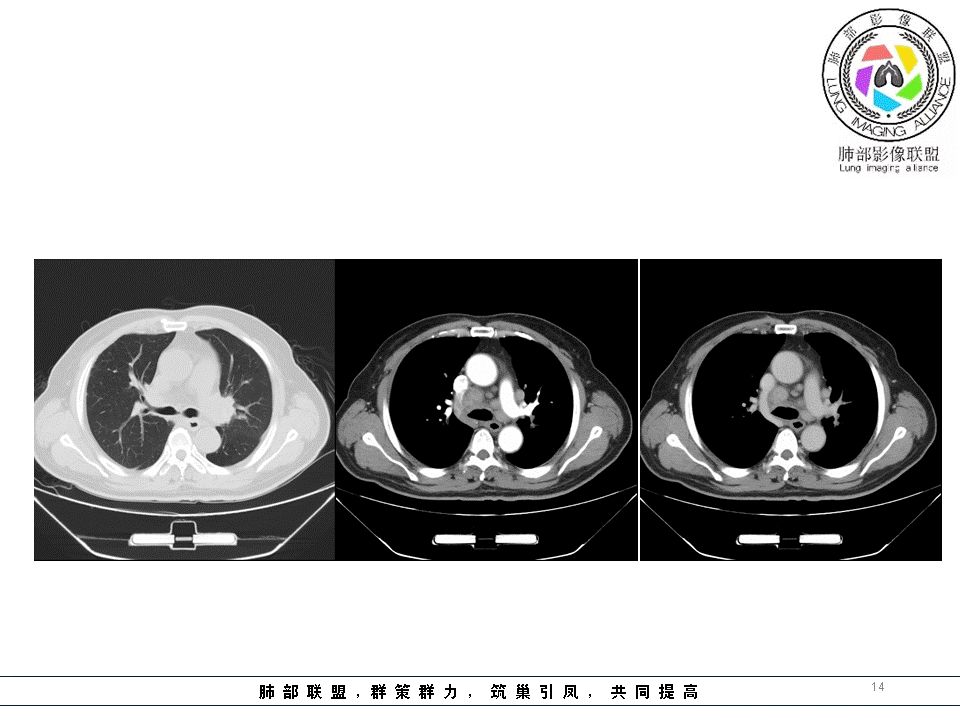

但是有一个地方有问题的,左侧的上叶的下舌段这个区域:

左上叶舌段这个气管腔内是有东西凸进去。

首先弥漫性的,支气管壁是一个问题,然后有病灶凸向腔内,那又是一个问题,我有两种想法。

1、支气管壁本身有问题,2周围淋巴结侵犯支气管壁